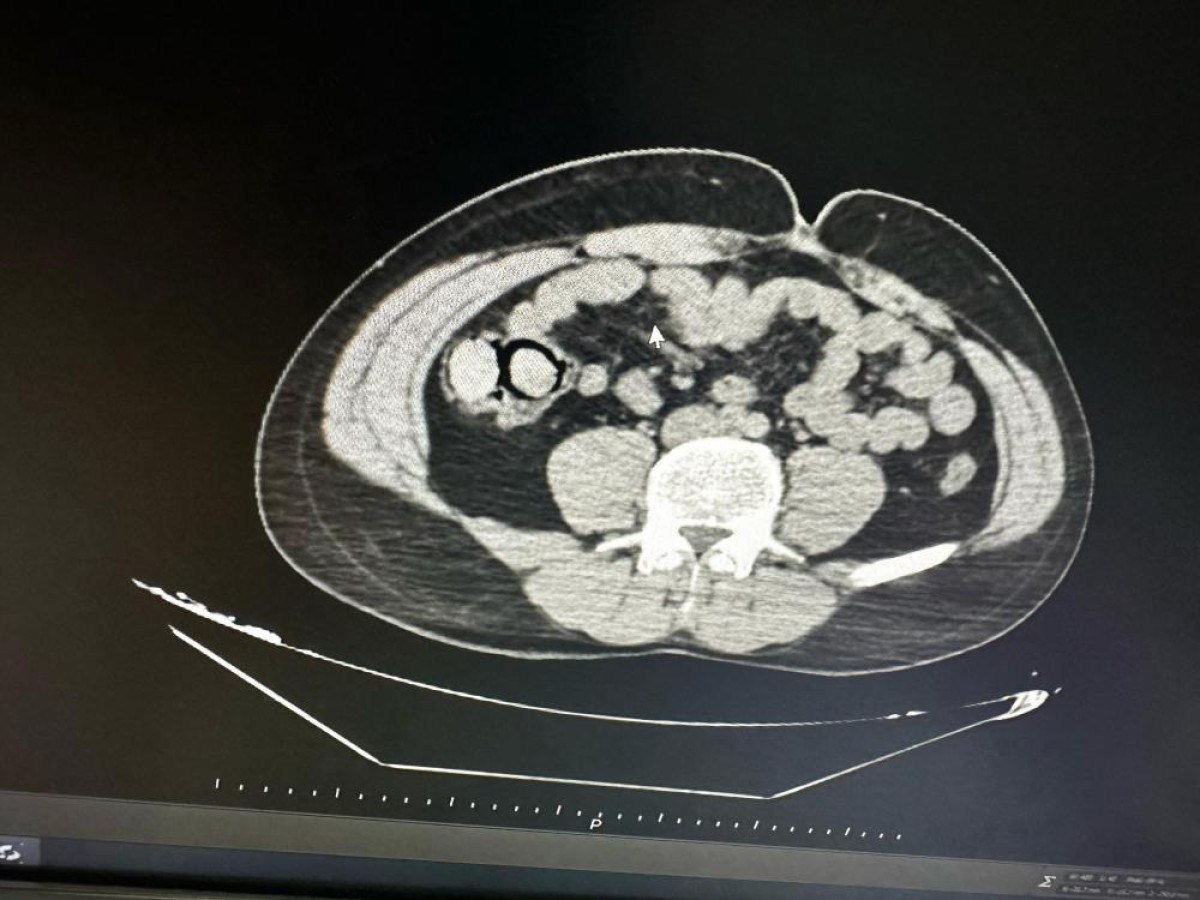

MİDESİNDEN 10 PAKET UYUŞTURUCU ÇIKTI

Gerçekleştirilen iç beden muayenesinde, 10 parça halinde toplam 113 gram metamfetamin ele geçirildi. Gözaltına alınan şahıslar, emniyetteki işlemlerinin ardından çıkarıldıkları mahkemece “uyuşturucu madde ticareti yapmak” suçlamasıyla tutuklanarak Elazığ Kapalı Ceza İnfaz Kurumu’na gönderildi.